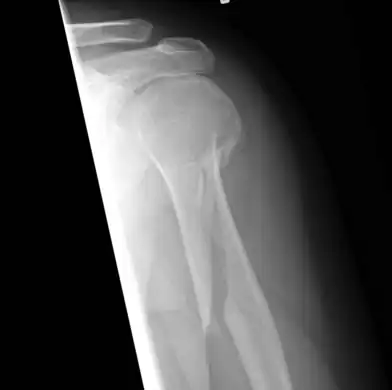

An x-ray image of a spiral fracture to the left humerus of a 27-year-old male. The injury was sustained during a fall.